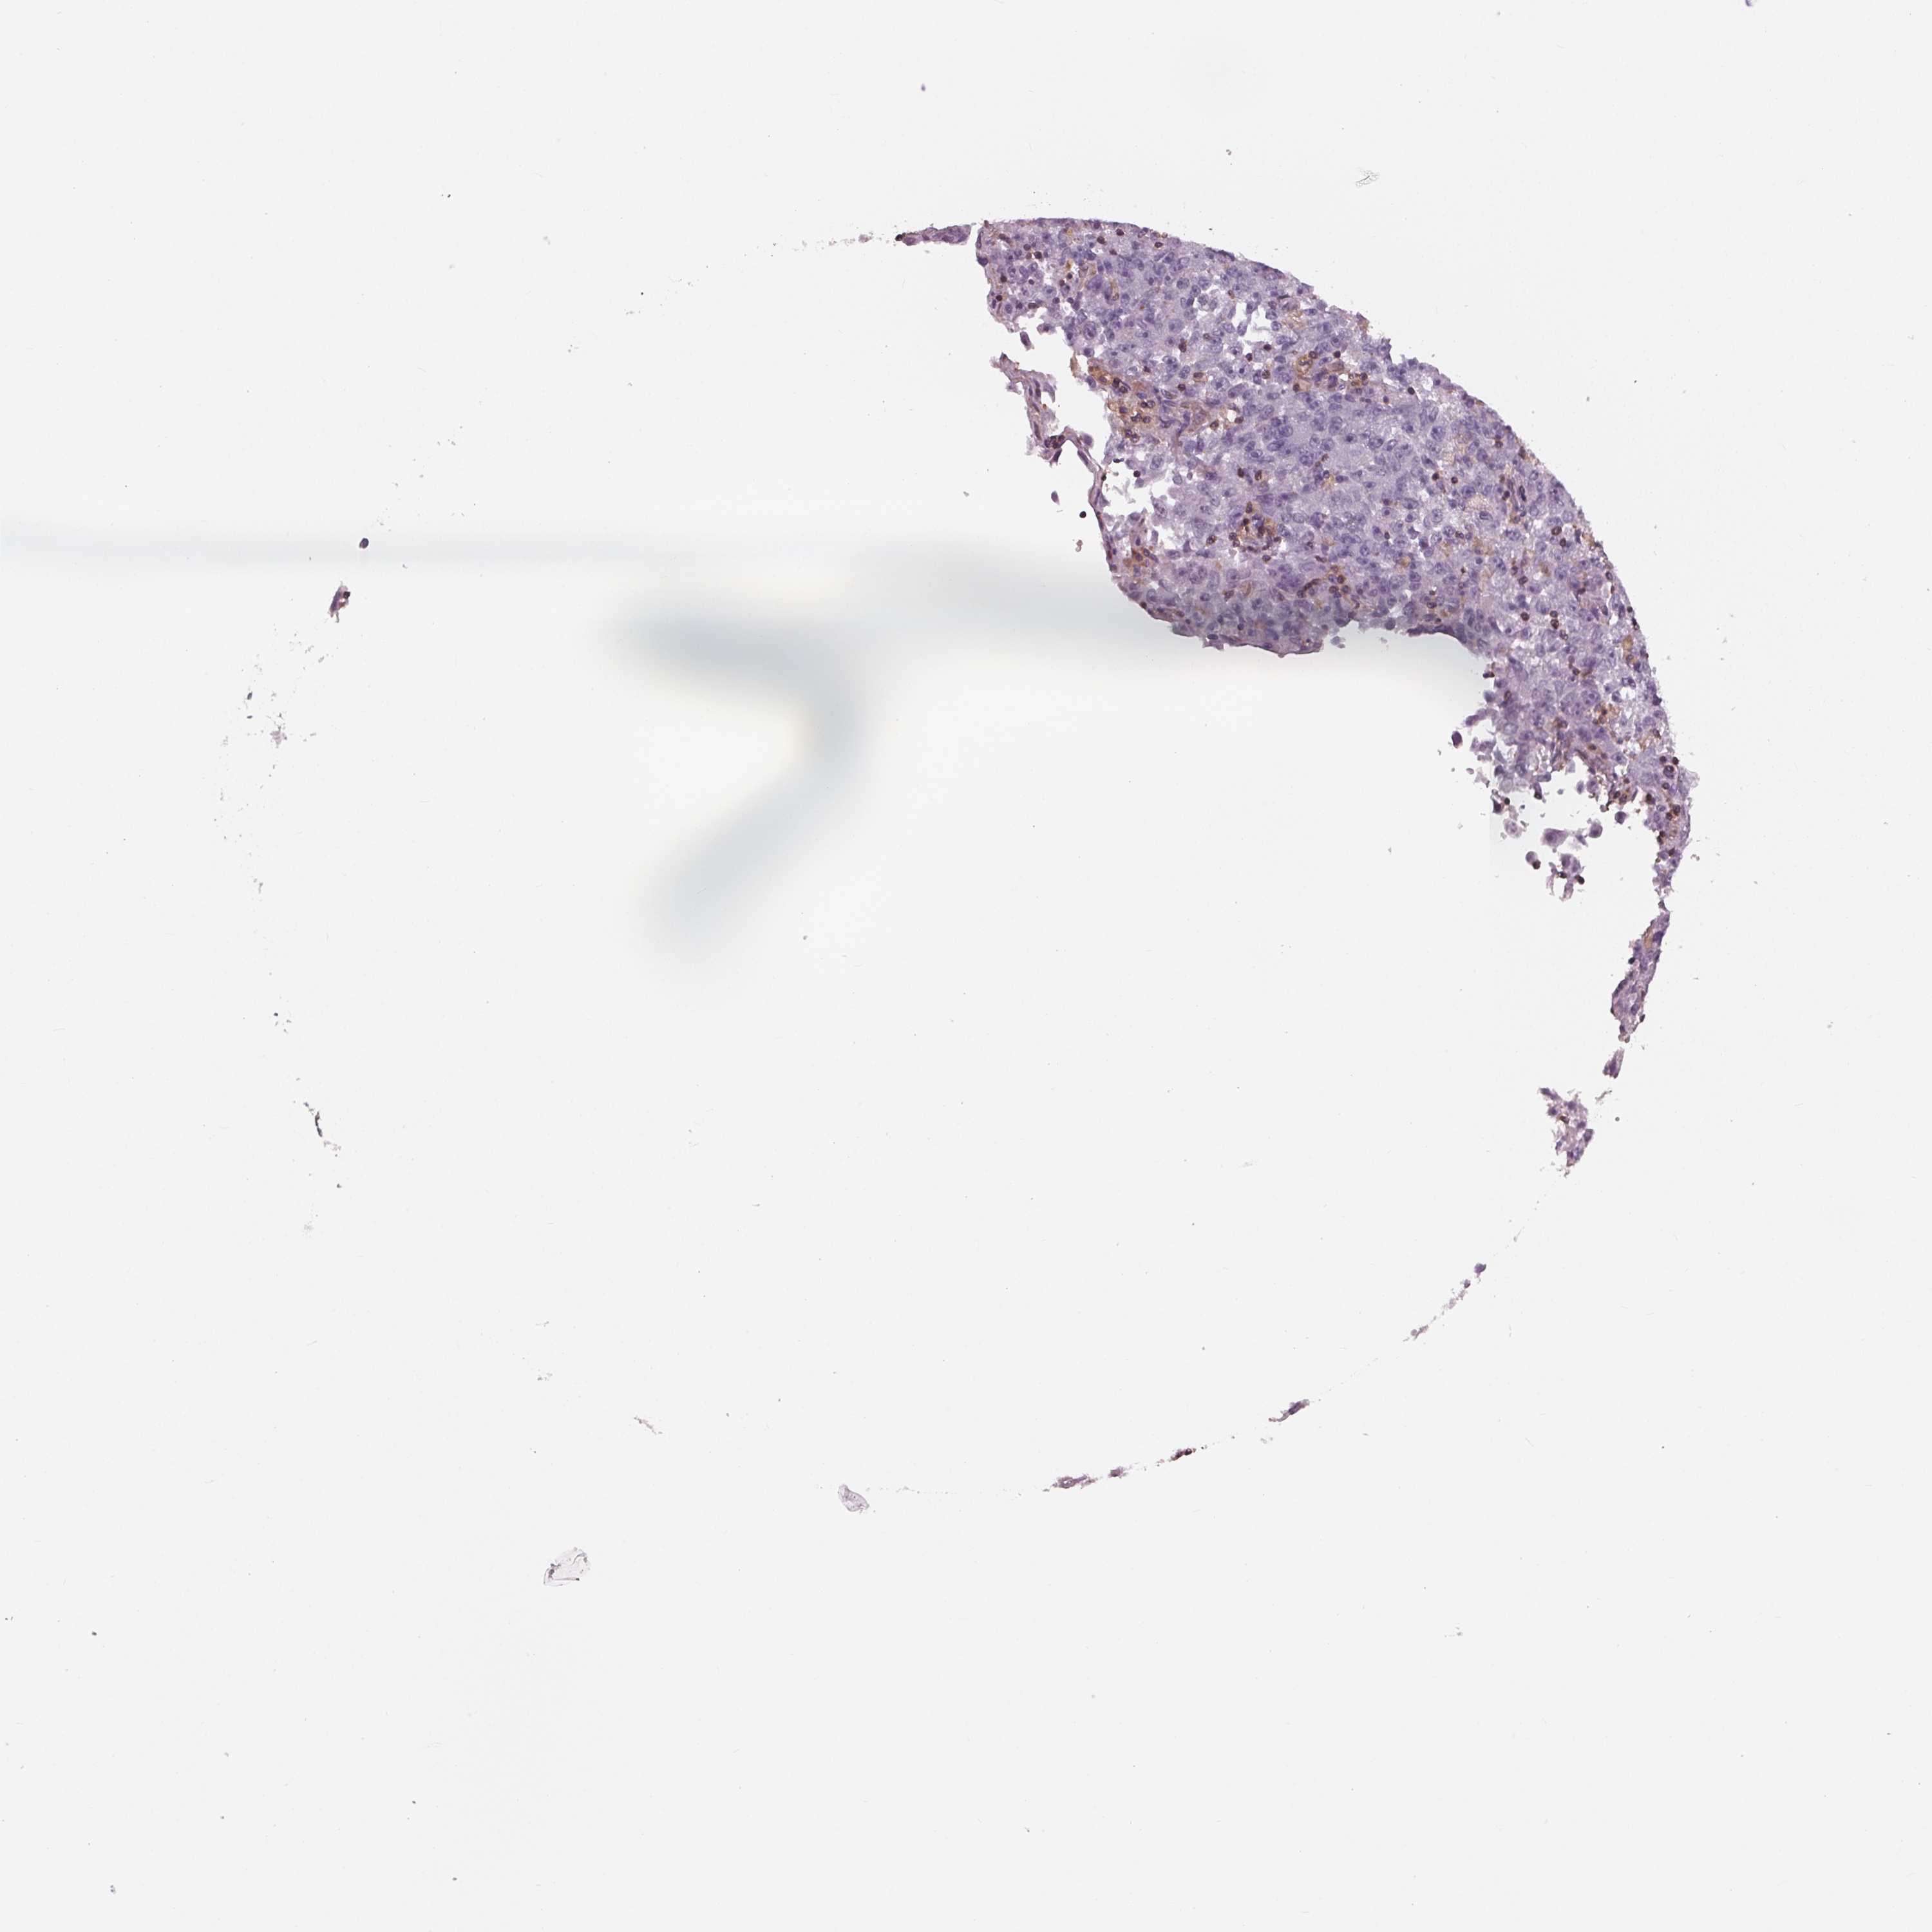

LUNG SQUAMOUS CELL CARCINOMA (TCGA) - Interactive survival scatter ploti

The Survival Scatter plot shows the clinical status (i.e. dead or alive) for all individuals in the patient cohort, based on the same data that underlies the corresponding Kaplan-Meier plots. Patients that are alive at last time for follow-up are shown in blue and patients who have died during the study are shown in red.

The x-axis shows the expression levels (FPKM) of the investigated gene in the tumor tissue at the time of diagnosis. The y-axis shows the follow-up time after diagnosis (years). Both axes are complimented with kernel density curves demonstrating the data density over the axes. The top density plot shows the expression levels (FPKM) distribution among dead (red) and alive patients (blue). The right density plot shows the data density of the survived years of dead patients with high and low expression levels respectively, stratified using the cutoff indicated by the vertical dashed line through the Survival Scatter plot. This cutoff is automatically defined based on the FPKM cutoff that minimizes the p-score. The cutoff can be changed by dragging the vertical line or by entering a cutoff value in the square labeled "Current cut-off".

Under the Survival Scatter plot the p-score landscape (black curve; left axis) is shown together with dead median separation (red curve; right axis). Dead median separation is the difference in median mRNA expression between patients who have died with high and low expression, respectively. It is calculated as follows: median FPKM expression of dead patients with high expression - median FPKM expression of dead patients with low expression. This is intended to aid the user in visually exploring custom cutoffs and the associated p-scores and dead median separation.

Individual patient data is displayed and can be filtered by clicking on one or more of the category buttons on the top of the page. Categories describing expression level and patient information include: high, low, alive, dead, female, male and tumor stages. The scale of the x-axis can be toggled between linear and log-scale by clicking on the "x log" button. Mouse-over function shows TCGA ID, patient information and mRNA expression (FPKM) for each patient.

& Survival analysisi

Kaplan-Meier plots summarize results from analysis of correlation between mRNA expression level and patient survival. Patients were divided based on level of expression into one of the two groups "low" (under cut off) or "high" (over cut off). X-axis shows time for survival (years) and y-axis shows the probability of survival, where 1.0 corresponds to 100 percent.

ARHGAP25 is not prognostic in Lung Squamous Cell Carcinoma (TCGA)

Best expression cut offi

: 6.64

Average pTPM 10.5

Number of samples 489